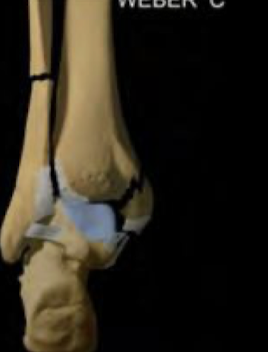

Weber C

Fx de peroné por encima del nivel del plafón tibial